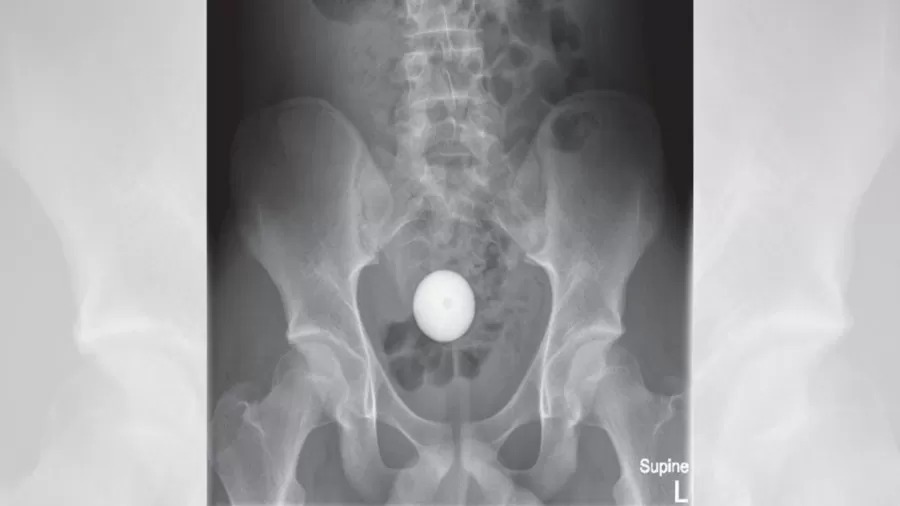

Um adolesente de 14 anos foi parar no hospital após inserir uma bola de golfe no próprio ânus e o objeto ficar preso em seu intestino grosso. O caso aconteceu na Austrália.

A equipe médica chegou a usar seis ferramentas diferentes para retirar a bola, que foi parar no intestino grosso do rapaz. Chegaram a ser utilizadas uma ventosa, uma rede médica, uma pinça de quatro pinos e um cateter de balão.

Após horas de tentativas, os profissionais do hospital desistiram de remover o objeto manualmente e decidiram esperar que ele saísse espontaneamente. Novos raios-X realizados no dia seguinte mostraram que a bola permanecia no cólon do rapaz. Com isso, os médicos passaram a administrar uma grande quantidade de laxantes ao menino. Foi apenas após receber 1 litro de medicações de ação laxativa que ele conseguiu evacuar a bola de golfe. Ele recebeu alta no mesmo dia, depois de apresentar bom quadro clínico não ser constatada lesão no cólon.